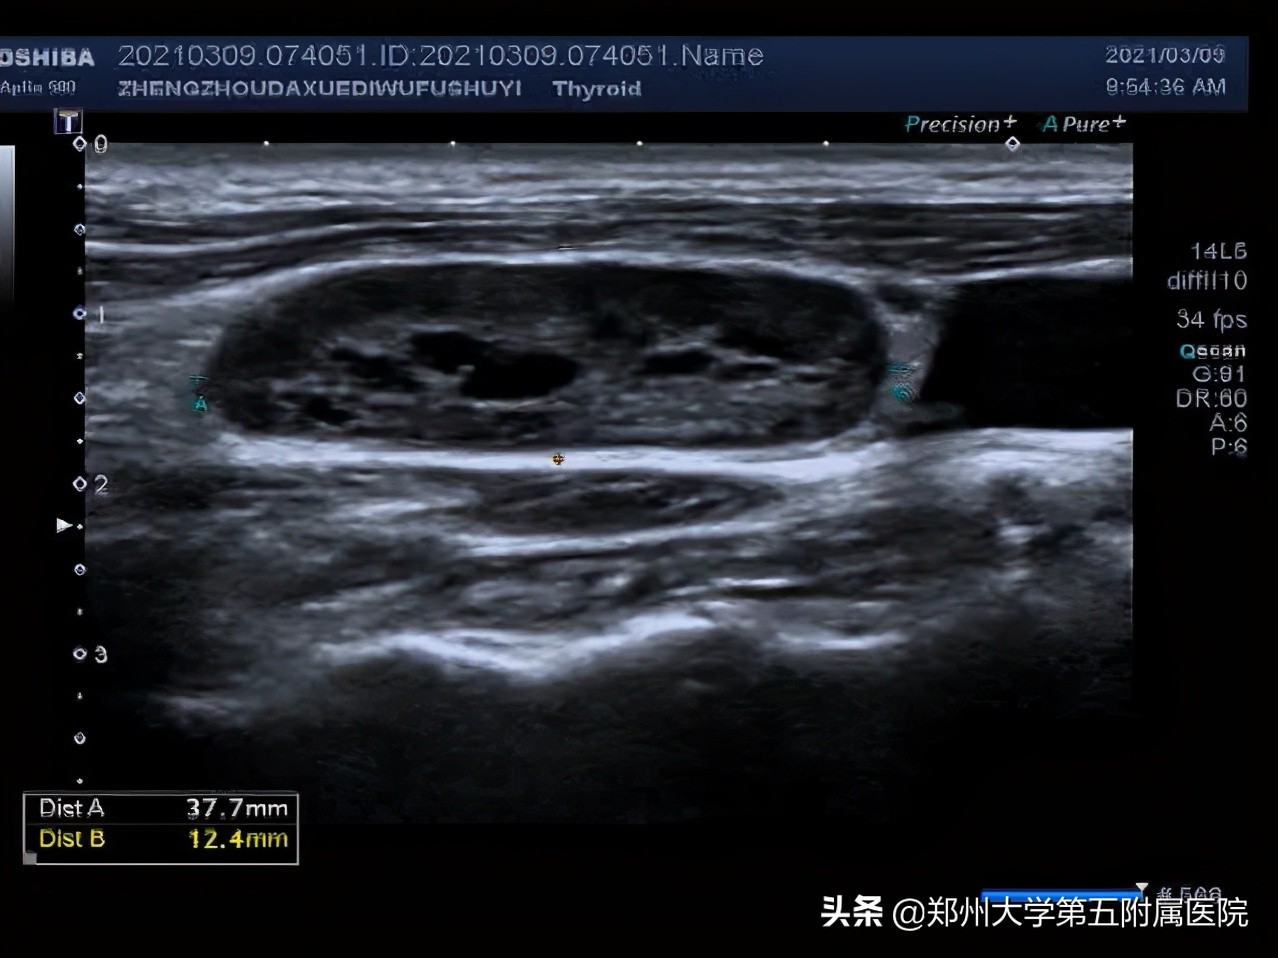

1.淋巴结皮髓质分界不清

2.淋巴结内部有液化

3.淋巴结血流为周边型,没有淋巴门。

2.不疼不痒、进行性肿大淋巴结:这些淋巴结要注意了!需要到医院做彩超检查,检查前不需要特殊准备。超声看到淋巴结内有液化、钙化、淋巴结变圆,皮髓质分界不清,淋巴结相互融合、淋巴结血流为周边型、淋巴门消失等就可能是淋巴瘤、结核、转移性肿瘤、结节病等,需告知临床医生进行进一步检查明确诊断。